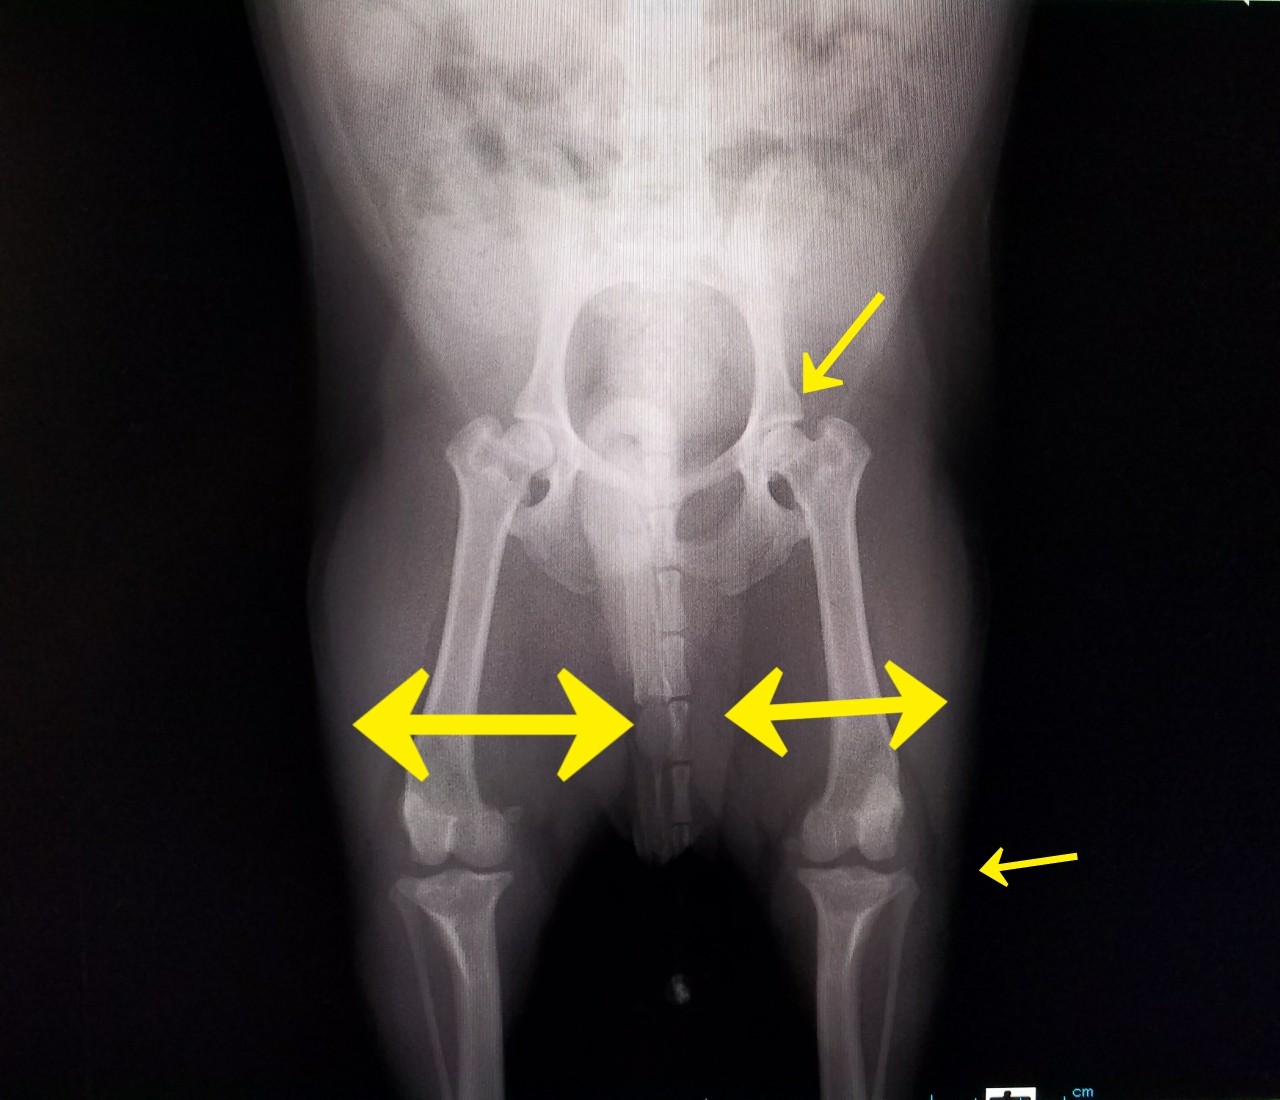

ゆきち君のレントゲン

所見:

①筋肉の付き方が右左、差がある。

②股関節のところが若干おかしい

レントゲン その②

種子骨(いいのか?これでいいのか?)の位置がおかしい。

(左が正常で右がおかしい。)

ということだった。

この種子骨の位置は、今回のエピソードでここまできちゃったのか? それとも、生まれつきなのかははっきりせずでした。

あんまり見ない症例らしい。

右の筋肉が痩せてるのは、普段からあまり右をかばってつかっていなかったのでしょうかぁ?